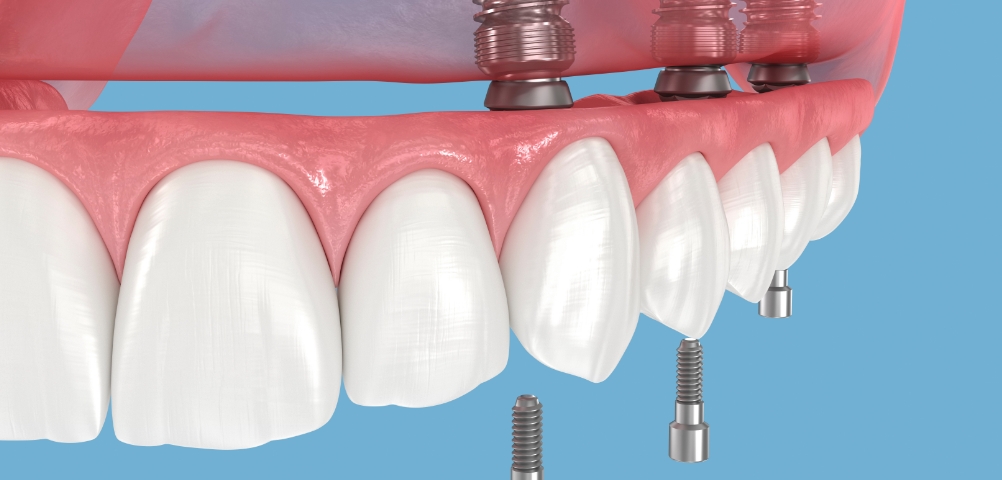

임플란트는 정확한 진단과 계획을 기반으로

여러 단계를 거쳐 진행되는 치료입니다.

환자분의 구강 상태에 맞춰

단계별로 안전하게 진행됩니다.

계획된 가이드에 따라 안정적으로

임플란트를 식립합니다.

임플란트는 난이도가 높은 치료인 만큼 정밀한 검사와 충분한 계획이 필수적입니다.

따라서 풍부한 임상 경험과 노하우를 갖춘 의료진에게 받는 것이 중요합니다

임플란트를 식립하는 날, 필요한 검진·계획 후 바로 식립까지 진행되는 방식입니다.

※ 환자 개개인의 잇몸뼈·치주·전신 건강 상태에 따라 가능 여부는 달라질 수 있습니다.